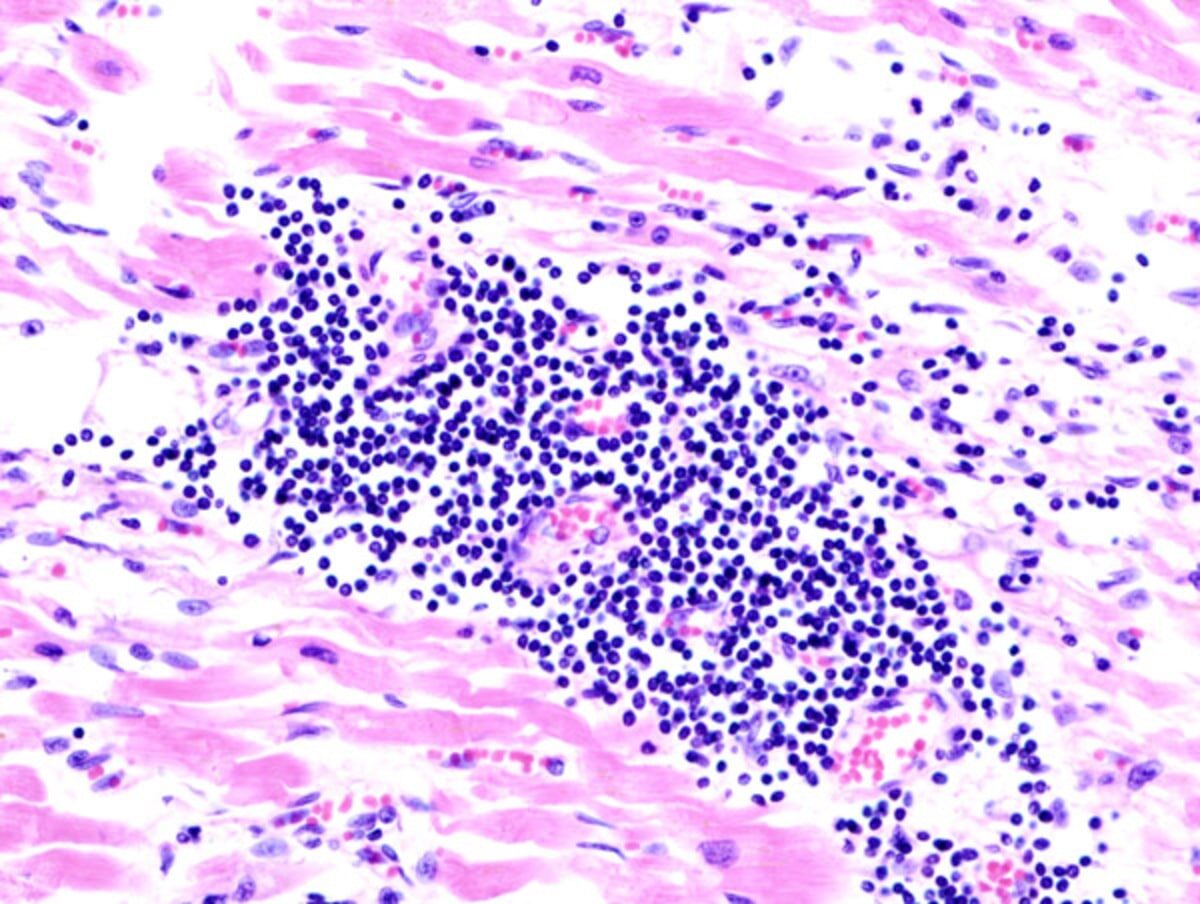

Микрография миокардита / © BellRap, Wikipedia